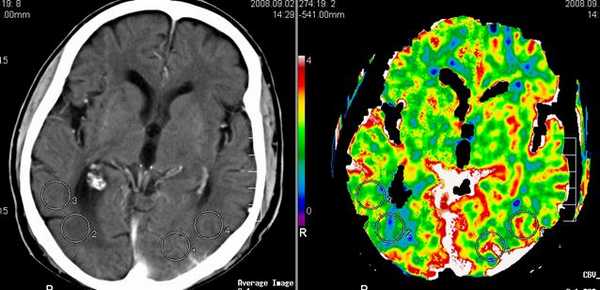

Перфузионно-взвешенные МРТ во многом аналогичны перфузионным изображениям при КТ. Т2-градиентные МРТ отражают магнитную чувствительность. Яркий сигнал на ДВИ МРТ коррелирует со снижением кровотока на перфузионно-взвешенных МРТ головного мозга.

МРТ головного мозга. Перфузионно-взвешенная МРТ. Снижение кровотока в левой лобной доле.

МРТ головного мозга. Сопоставление диффузионно-взвешенной и перфузионно-взвешенной МРТ.